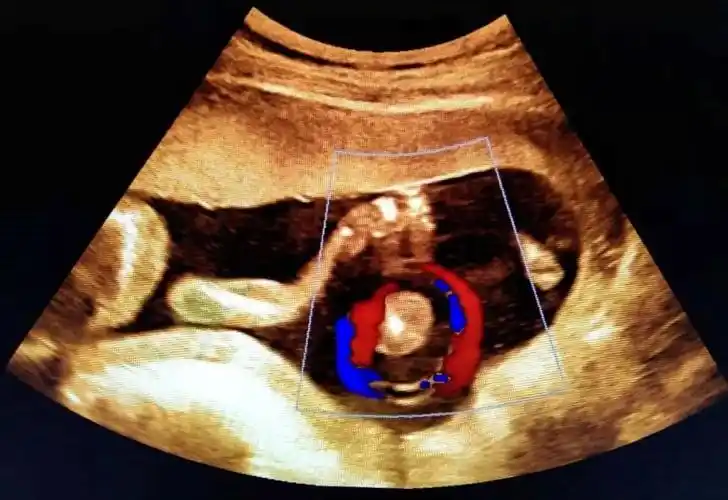

脐带缠绕超声如图所示:脐带绕颈对胎儿的影响视其缠绕松紧程度而不同

超声诊断脐带缠绕